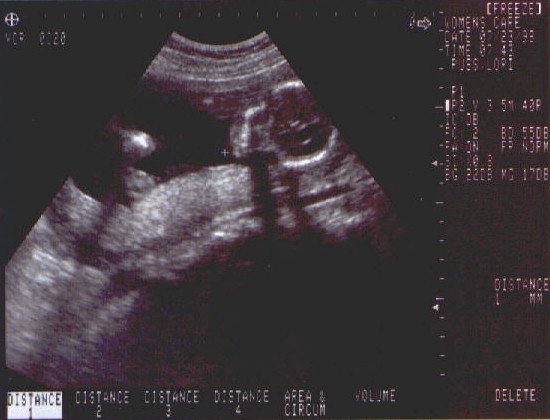

• 23rd July 1998 - Second and final ultrasound today (if nothing goes wrong).  We got to see a healthy developing baby girl.  Brain, heart, skeletal and organ development is on track and looking good.  We decide on the name for sweet pea - Caitlin Elizabeth Russ.  Take a look at the sonograms we have from the ultrasound.

Click here for full size picture!

A nice shot of Sweet Pea's face.  (I think she is smiling ;-)